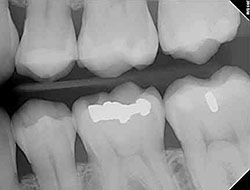

Bonding is a conservative way to repair slightly chipped, discolored, or crooked teeth. During dental bonding, a white filling is placed onto your tooth to improve its appearance. The filling "bonds" with your tooth, and because it comes in a variety of tooth-colored shades, it closely matches the appearance of your natural teeth.

Tooth bonding also can be used for tooth fillings instead of amalgam fillings. Many patients prefer bonded fillings because the white color is much less noticeable than the silver amalgam fillings. Bonding fillings can be used on front and back teeth depending on the location and extent of tooth decay.

Fillings

Traditional dental restoratives, or fillings, may include gold, porcelain, and composite. The strength and durability of traditional dental materials continue to make them useful for situations where restored teeth must withstand extreme forces that result from chewing, such as in the back of the mouth.

Newer dental fillings include ceramic and plastic compounds that mimic the appearance of natural teeth. These compounds, often called composite resins, are usually used on the front teeth where a natural appearance is important, as well as on the back teeth depending on the location and extent of the tooth decay.